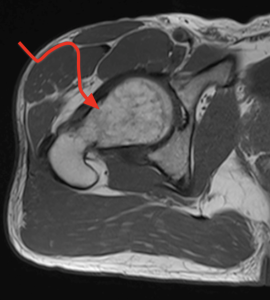

La prothèse de hanche est une intervention chirurgicale couramment pratiquée par le Dr Gastaud pour remplacer une articulation de la hanche endommagée ou usée. Cette procédure est généralement recommandée pour les personnes souffrant d’arthrose, d’arthrite rhumatoïde, de nécrose de la tête fémorale ou de fractures graves de la hanche.

La prothèse de hanche consiste en la mise en place de composants artificiels qui reconstituent l’articulation de la hanche. Elle vise à réduire la douleur, améliorer la mobilité et augmenter la qualité de vie des patients.

Les personnes souffrant d’affections articulaires telles que l’arthrose, l’arthrite rhumatoïde, la nécrose de la tête fémorale ou ayant subi des fractures graves de la hanche sont les plus à risque et peuvent bénéficier de la prothèse de hanche.

Le diagnostic de la nécessité d’une prothèse de hanche est établi par un examen clinique approfondi, des radiographies et éventuellement d’autres examens d’imagerie. Le Dr Gastaud évaluera votre condition médicale pour déterminer si une prothèse de hanche est appropriée.